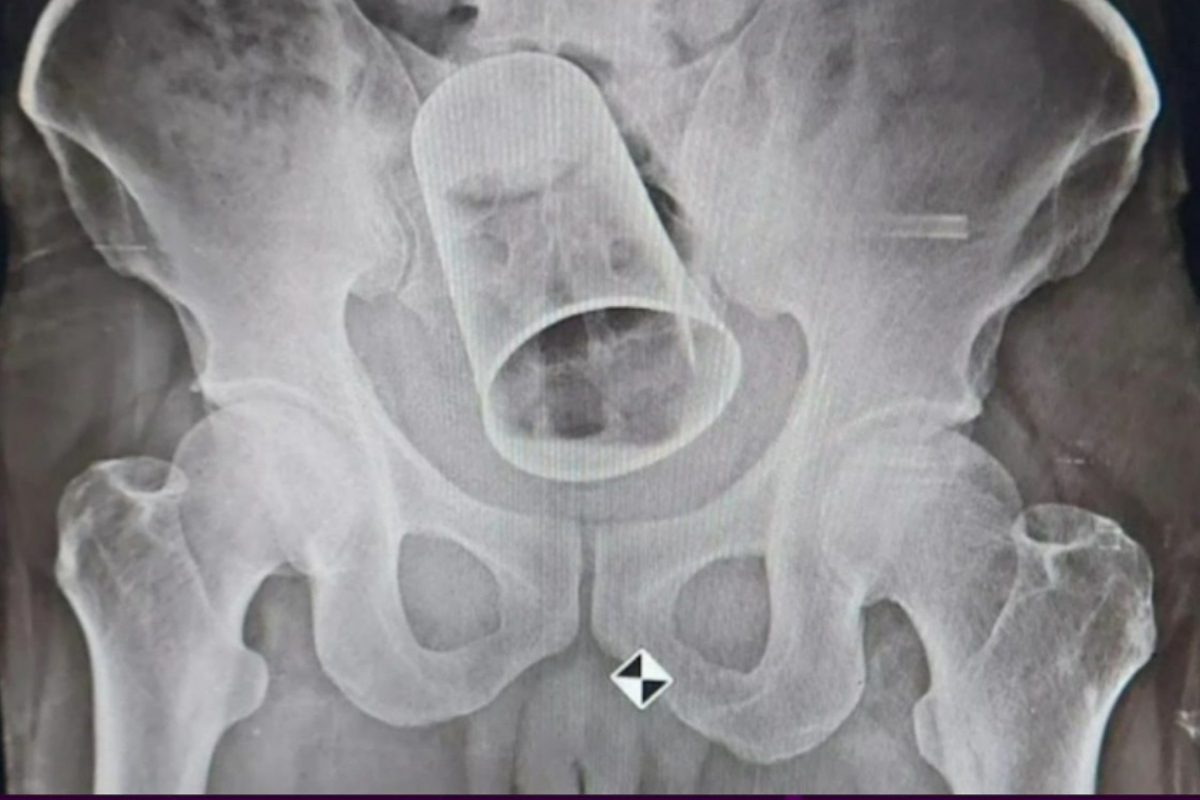

Steel glass surgically removed from a man’s rectum after 10 days

Steel glass

Glass was stuck in Krushna Rout’s rectum, which is the last few inches of the large intestine. After 10 days, when he went back to Odisha, he had surgery to get the glass out. Hospital sources say that he is getting better. A strange and potentially dangerous act done in the name of “friendship” almost … Read more